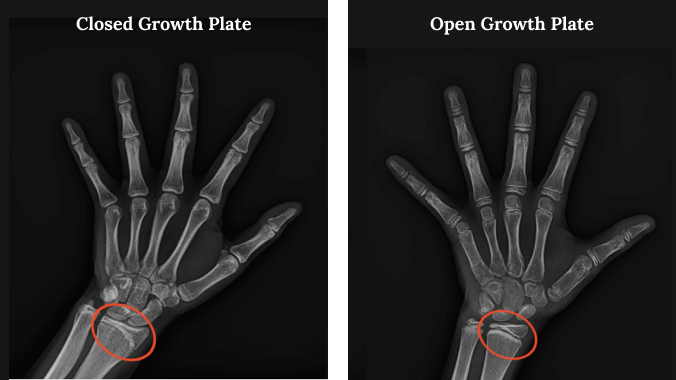

Yes they are closing but it looks like they almost completely binded

explainnot closed yet

yours are almost fully closed however this ai estimates 15 years 1 month to 16 years 1 month